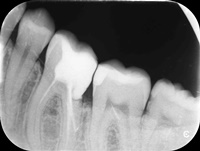

Reendo 14.

Pacjentka zgłosiła się z bólem. Kilka miesięcy wcześniej leczona kanałowo lewa dolna szóstka. Ząb wrażliwy na nagryzanie. Podjęto decyzję o ponownym przeleczeniu kanałów korzeniowych. Zamknięto perforację przy wejściu do dalszego kanału, usunięto złamaną igłę lentulo z dalszego kanału, udrożniono mezjalne kanały, aż do perforacji korzenia w policzkowym bliższym kanale. Wypełniono dalszy kanał gutaperką, bliższe kanały wypełniono MTA. Ząb do obserwacji, najprawdopodobniej będzie wykonana resekcja wierzchołków bliższego korzenia, na poziomie perforacji.